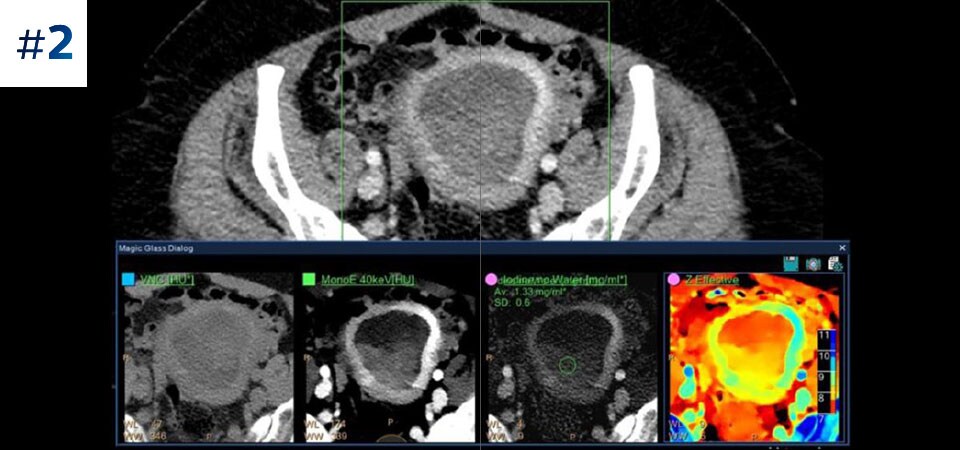

A study showed a 96% increase in diagnostic certainty when differentiating benign cysts from malignant lesions when using spectral dual-layer detector CT versus 30% with conventional CT.1

Unlike source-based spectral options, detector-based approaches simultaneously absorb and differentiate high and low energy, available in a single polyenergetic X-ray beam, at the detector level. Spectral results are acquired within a single scan without the need for special modes.

Retrospective analysis for results on demand with no trade-offs